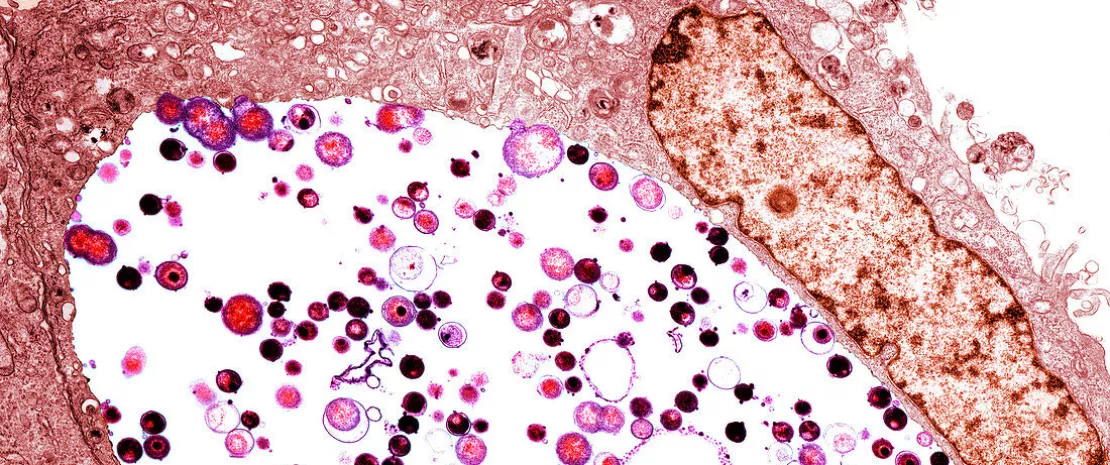

They followed participants before, during, and after an incident Chlamydia infection. But rather than just charting symptoms or behaviors, they analyzed the entire microbial community of the cervicovaginal tract using high-resolution 16S rRNA and ITS1 gene sequencing.

The team used a powerful molecular algorithm (molBV) to quantify bacterial vaginosis (BV)-like states, then categorized microbial communities into “Community State Types” (CSTs).

Among these, CST-IV-A, dominated by Candidatus Lachnocurva vaginae, emerged as the microbial signature most strongly associated with incident Chlamydia infection.

When CST-IV-A overlapped with a high molBV score, a state dubbed mBV-A, the risk of acquiring Chlamydia skyrocketed. Women with this mBV-A profile had more than double the risk of infection compared to those with a Lactobacillus-dominant microbiome (e.g., L. crispatus).

Even more striking? This elevated risk existed months before infection, revealing mBV-A not as a result of Chlamydia, but as a harbinger. This microbial landscape, characterized by high diversity and a drop in protective Lactobacilli, undermines the vaginal environment's natural defenses. It’s not just about pH or lactic acid.